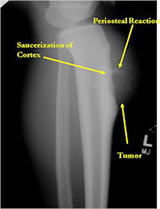

Plain X-Rays:

- Diaphyseal lesion on external surface of bone; medullary canal uninvolved

- Radiolucent mass extending into surrounding soft tissues

- Saucerized cortex with chondroblastic soft tissue mass that is usually primarily radiolucent on plain X-rays

- Periosteal reaction usually most evident feature on surface of bone (Hair on End or Sunburst appearance with spiculated pattern of calcification oriented perpendicular to the bone)

- Cortical thickening at margins of erosion (40%)

- Spiculated or sunburst periosteal reaction (due to periosteal elevation)